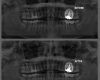

Root canal therapy is a type of dental procedure that has been around for some time. In fact, it is one of the most frequently performed dental procedures in the country. Nearly 15 million people each and every year have this type of procedure performed as a way to save their natural teeth. Most importantly, by having root canal therapy, an individual can avoid the expense and complexity of dental implants or bridges. Read more

While the success rate for endodontic treatment is considered very high, there are certain instances and cases where pain may persist long after the initial treatment has been completed. This is when endodontic retreatment may be required. For example, if a cracked or loosened restoration exposes the tooth to a new infection, retreatment may be necessary. This type of procedure may also be required when new trauma exists, thus exposing the root canal filling material and thereby resulting in infection. Read more

Endodontic surgery or apicoectomy involves the specialist making an incision in the gum tissue to expose the bone as well as the surrounding tissue that may have become inflamed. During the surgery, damaged tissue is carefully removed along with any damaged or injured root. In most situations only the root tip must be removed. The next step involves replacing any part of the tooth root that has been removed with a suitable filling material. Full function is restored once the bone surrounding the root has had time to heal and regenerate. Read more